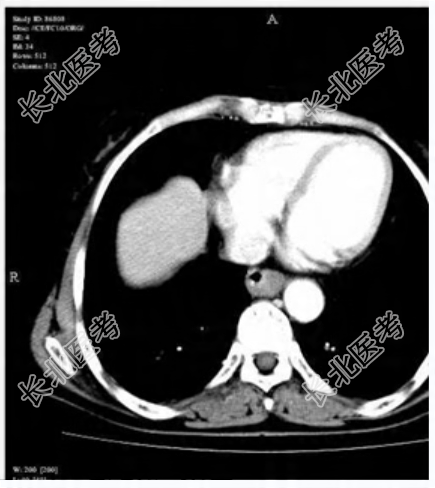

- 单项选择题女性患者,66岁。进行性吞咽困难1个月。如图所示, 最可能的诊断为

D、食管癌